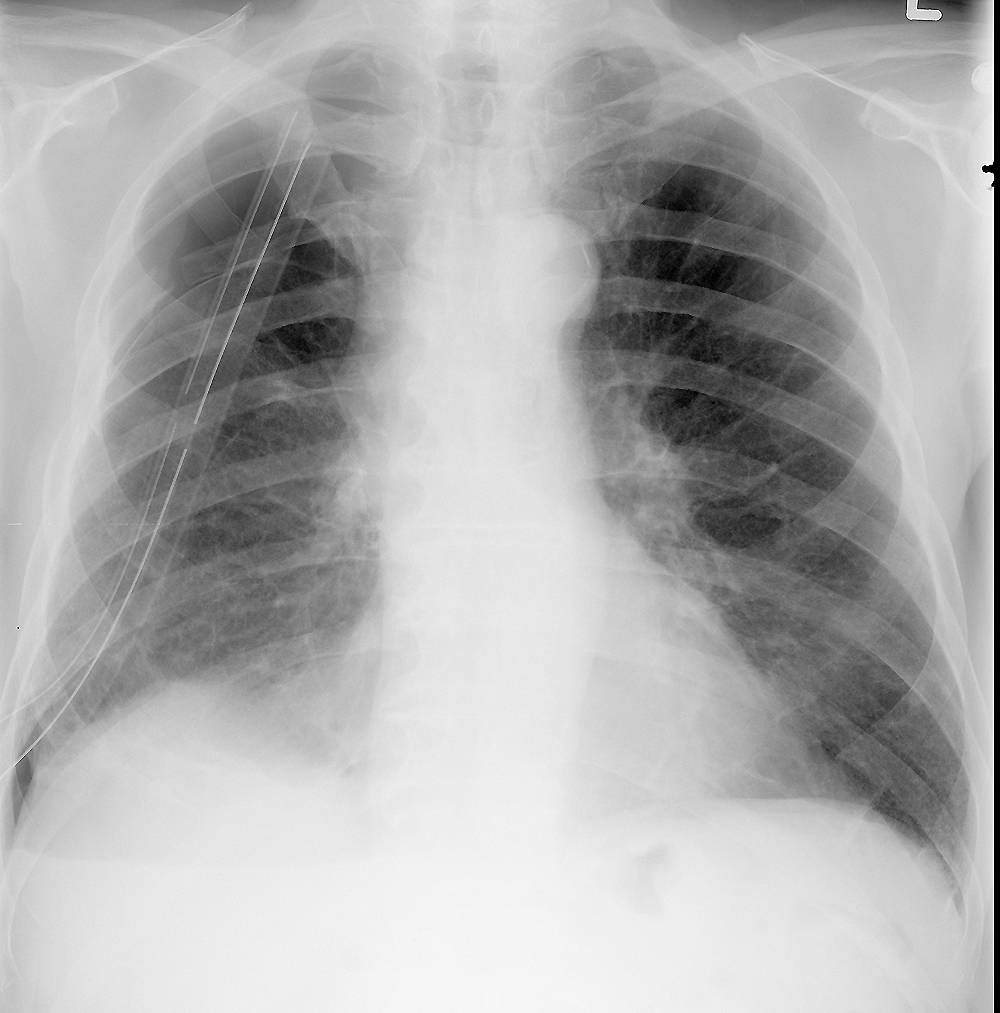

basic case for PTX